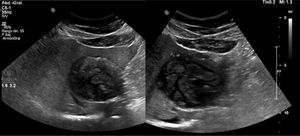

Presentamos el caso de una paciente de 37 años sin comorbilidades, refería convivencia con cerdos, perros y vacas. Inició un año previo a su padecimiento actual con dolor abdominal en epigastrio. Se le realizó un USG abdominal, con reporte de tumoración en lóbulo hepático izquierdo, por lo que fue referida a nuestro instituto. Como abordaje se realizó una TAC de hígado (fig. 1) encontrando una lesión quística compleja de 6.7×6.1cm que involucra segmentos 2, 3, contactaba segmento 4a, vena cava inferior y vena suprahepática media; asociado a zonas calcificadas y escasa grasa. Se complementó con ultrasonido hepático (fig. 2) y RMN contrastada (fig. 3) reportando lesión compatible con quiste hidatídico, etapa CE4 de la clasificación de la OMS. Se solicitó serología para hidatidosis la cual fue negativa. La paciente se consideró candidata a hepatectomía lateral izquierda laparoscópica. Durante la cirugía se encontró quiste firmemente adherido a la vena cava inferior (fig. 4), en contacto estrecho con vena suprahepática media (fig. 5), sin involucro de la vía biliar. El resultado de la patología confirmó el diagnóstico de quiste hidatídico. Tuvo buena evolución posquirúrgica, egresando a los 3 días, completó 6 semanas de tratamiento postoperatorio con albendazol y seguimiento durante 6 meses.